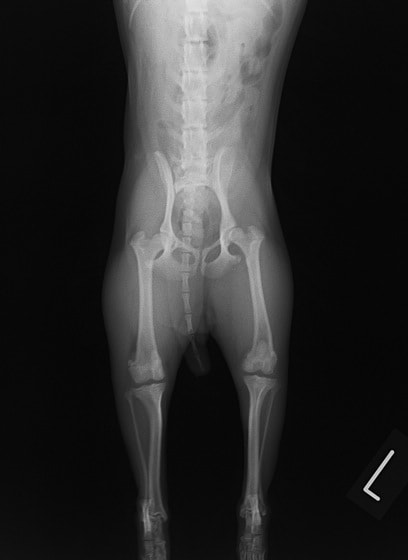

■ 症例22 ポメラニアン 1歳5か月 去勢雄

左後肢の挙上を主訴に来院した。整形学的検査、レントゲン検査より左右の膝蓋骨脱臼(左GradeⅡ〜Ⅲ、右Grade Ⅱ)を認めた。また、脛骨の前方引き出し試験の際に、引き出し兆候は認められないものの、疼痛が認められたため、前十字靭帯の損傷が疑われた。術中における、目視および関節内の操作によって、前十字靭帯の損傷や過伸展といった異常が認められなかったため、膝蓋骨脱臼の整復のみ実施した。手術手技は縫工筋及び内側広筋の解放、脛骨粗面の外側転位、滑車ブロック形造溝術、内外側関節包の縫縮を実施した。本症例は跛行もなく経過良好である。しかし、頸骨高平部の角度(TPA)が 右26.2°、左24.9°であり、解剖学的に前十字靭帯損傷のリスクが高いことから今後の経過に注意が必要である。